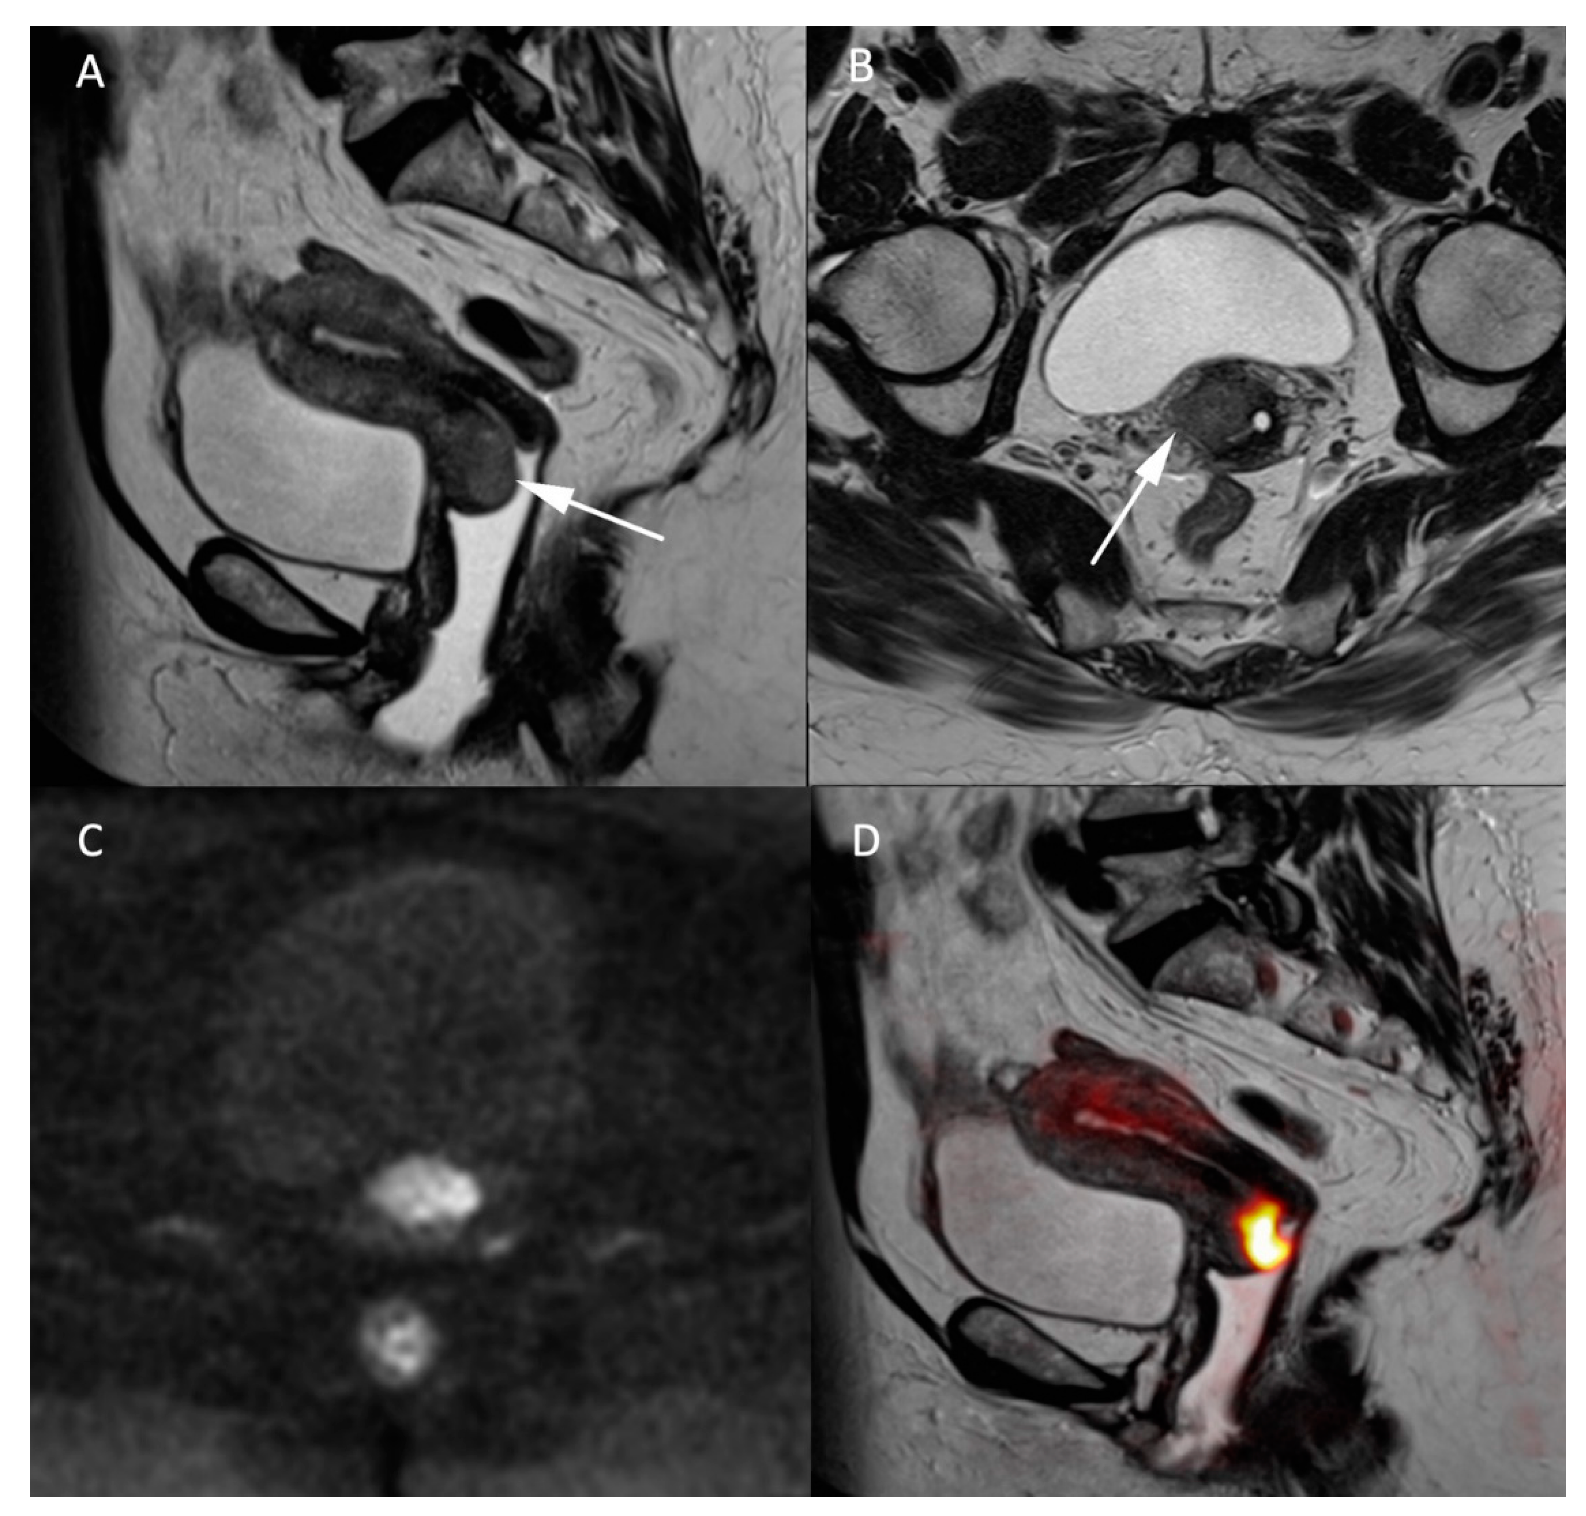

In addition to the morphologic T2W sequences, DWI is used to assess the local extension of the carcinoma and is equivalent to contrast-enhanced MRI [18]. The T2W axial oblique plane perpendicular to the long axis of the cervix is important in assessing parametrial invasion (stage IIB) and can be coregistered with the high b-value DW sequence to improve tumoral tissue delineation [19], as demonstrated in Figure 2. Cervical carcinomas are characterized by hypercellularity resulting in high signal intensity (SI) on high b-value (1000 s/mm2) DW images and a low Signal Intensity (SI) on the ADC map compared to normal cervical stroma [16]. So far, no ADC cutoff value has been validated to predict the presence of malignancy, mainly because of the mutual dependence between the calculated ADC value and the range of b-values used for calculation [16]. In the context of follow-up after local radiotherapy and systemic chemotherapy treatment, DWI is used to differentiate between residual disease and local fibrosis [20], as well as to detect tumor recurrence [21]. DWI may also be used as a biomarker for monitoring tumor response [22,23]. In a recent meta-analysis on the use of artificial intelligence (AI) in gynecologic tumors, cervical cancer was subject to a high number of studies (34 from 71) mainly focusing on the prognostic value of imaging [24]. As all MR sequences are exploited collectively in AI, it remains difficult to extrapolate on the specific utility of DWI within this kind of black box approach.

Figure 2.

MR images of a 66-year-old woman with a known cervical carcinoma. (A) Sagittal T2W image; (B) axial T2W image perpendicular to the cervical axis. Cervical cancer and its extension appearing as low-contrasted T2W area (arrow) through the normal stroma and the right parametrium, (C) high b-value (b = 1000 s/mm2) and (D) fusion images between T2W and high b-value sequences for better evaluation of the carcinoma’s extension.